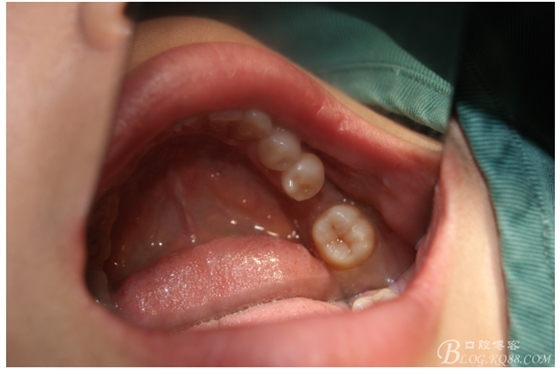

檢查:36.46缺失,36缺牙區(qū)近遠中間隙約3mm,46缺牙區(qū)間隙約0.5mm,37.47.48近中傾斜,48近中面齲壞達牙本質淺層,37牙周探診4mm,47近中探診深度5-6mm,不松,口內照片及CT片如下:

口內照片